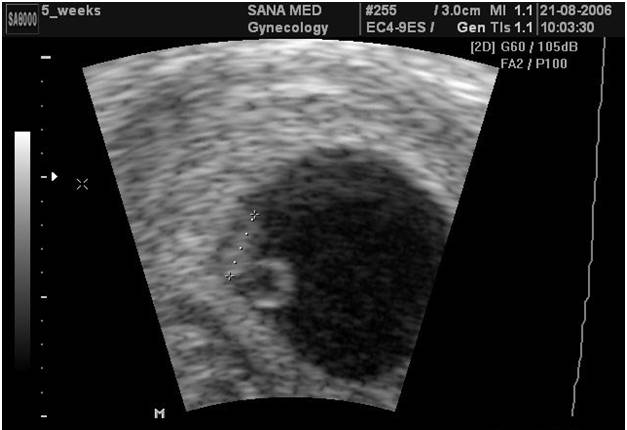

УЗИ на первой неделе беременности

Сказать со 100% уверенностью есть беременность или нет – может сказать только УЗИ

На самом деле, не смотря на современные технологии и прогресса науки, УЗИ на таком раннем сроке не сможет дать точный ответ на вопрос “беременна ли женщина или нет?”. На первой неделе после зачатия возможно провести ультразвуковое исследование для выявления овуляции и состоянии желтого тела, которое будет питать нашу клеточку в течение первой недели, поэтому нет необходимости проводить такие диагностические исследования на первой неделе после зачатия.